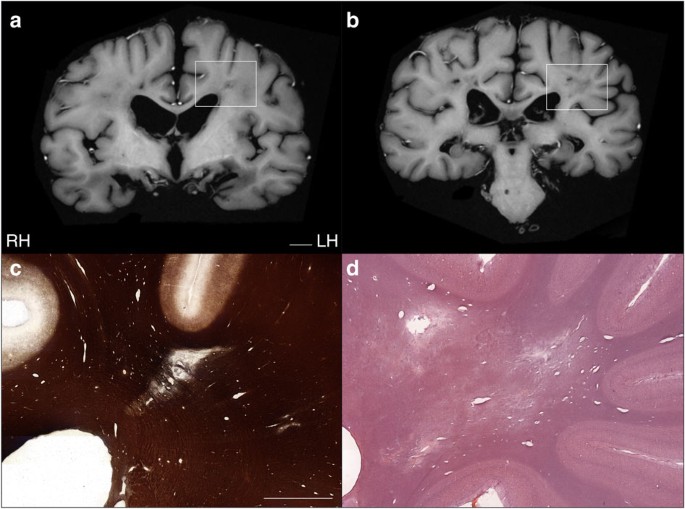

Кое-что разглядеть удалось (вы видите показанные поражения стрелкой), однако полную картину ученые так и не получили. Только после смерти мозг Молисона вновь был подвергнут испытаниям: сначала он, в зафиксированном состоянии был изучен на трёх- и семитесловом томографе, что дало исключительное качество картинки (см. фото внизу), а затем исследователь Джакомо Анезе совершил настоящий научный подвиг: 53 часа резал на микротоме замороженный мозг Молисона на 2401 срез толщиной в 70 микрон каждый. Удивительно, что исследователь «запорол» только два образца. И теперь ученые смогли построить полную карту поражений мозга Молисона.